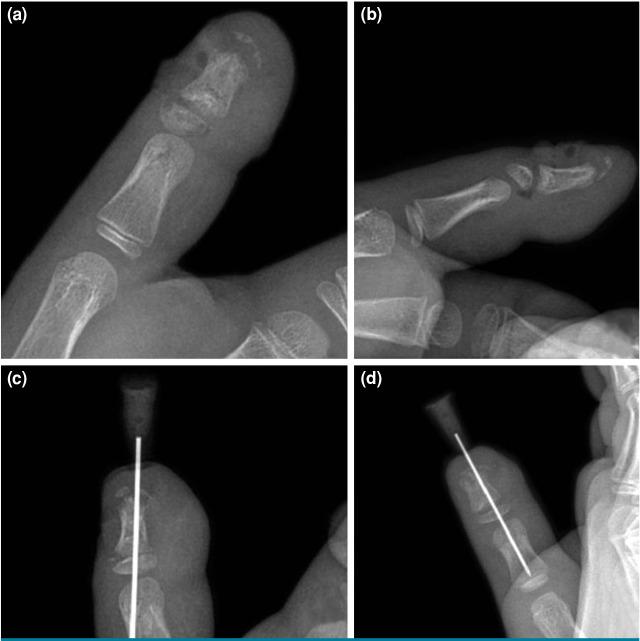

{"title":"The silent threat under the nail: Evaluation of Seymour fractures in pediatric patients.","authors":"Ahmet Yiğitbay, Gökhan Yıldırım, Muhammed Can Ari, Hakan Çetin, Cemal Kural","doi":"10.52312/jdrs.2025.2066","DOIUrl":null,"url":null,"abstract":"<p><strong>Objectives: </strong>This study aims to examine the diagnosis, treatment methods, and outcomes of Seymour fractures and to address diagnostic challenges in these fractures.</p><p><strong>Patients and methods: </strong>Between January 2020 and November 2023, a total of 28 pediatric patients (18 males, 11 females; mean age: 6.8±4.5 years; range, 1 to 15 years) who presented with Seymour fractures within 24 h of injury were retrospectively analyzed. Patients were treated either conservatively in the emergency department or surgically in the operating room if closed reduction was unsuccessful. All patients received intravenous antibiotics within the first 24 h, followed by oral antibiotics after discharge. Infection rates, physeal arrest, and nail dystrophy were evaluated during follow-up.</p><p><strong>Results: </strong>The mean follow-up was 16.6±6.6 (range, 12 to 32) months. There was no statistically significant difference in the affected side (right/left) and fingers (p=0.43 and p>0.05, respectively). The complication rate was significantly higher in surgically treated patients compared to those treated conservatively (p=0.02 and p<0.05, respectively). Evaluation of patients based on finger mobility showed no motion loss in the conservatively treated group at the final follow-up. In the surgically treated group, however, motion restrictions were noted in only two patients. Early antibiotic administration within 24 h significantly reduced infection rates, with only 3.5% (n=1) of patients developing osteomyelitis.</p><p><strong>Conclusion: </strong>Stable Seymour fractures can be treated conservatively in the emergency setting, while complex cases may require surgical intervention in the operating room. Early antibiotic use is essential in minimizing infection risk. Antibiotherapy within the first 24 h after injury is an effective way to prevent infection.</p>","PeriodicalId":73560,"journal":{"name":"Joint diseases and related surgery","volume":"36 2","pages":"320-327"},"PeriodicalIF":1.9000,"publicationDate":"2025-04-05","publicationTypes":"Journal Article","fieldsOfStudy":null,"isOpenAccess":false,"openAccessPdf":"https://www.ncbi.nlm.nih.gov/pmc/articles/PMC12086482/pdf/","citationCount":"0","resultStr":null,"platform":"Semanticscholar","paperid":null,"PeriodicalName":"Joint diseases and related surgery","FirstCategoryId":"1085","ListUrlMain":"https://doi.org/10.52312/jdrs.2025.2066","RegionNum":0,"RegionCategory":null,"ArticlePicture":[],"TitleCN":null,"AbstractTextCN":null,"PMCID":null,"EPubDate":"","PubModel":"","JCR":"Q2","JCRName":"ORTHOPEDICS","Score":null,"Total":0}

Patients and methods: Between January 2020 and November 2023, a total of 28 pediatric patients (18 males, 11 females; mean age: 6.8±4.5 years; range, 1 to 15 years) who presented with Seymour fractures within 24 h of injury were retrospectively analyzed. Patients were treated either conservatively in the emergency department or surgically in the operating room if closed reduction was unsuccessful. All patients received intravenous antibiotics within the first 24 h, followed by oral antibiotics after discharge. Infection rates, physeal arrest, and nail dystrophy were evaluated during follow-up.

Results: The mean follow-up was 16.6±6.6 (range, 12 to 32) months. There was no statistically significant difference in the affected side (right/left) and fingers (p=0.43 and p>0.05, respectively). The complication rate was significantly higher in surgically treated patients compared to those treated conservatively (p=0.02 and p<0.05, respectively). Evaluation of patients based on finger mobility showed no motion loss in the conservatively treated group at the final follow-up. In the surgically treated group, however, motion restrictions were noted in only two patients. Early antibiotic administration within 24 h significantly reduced infection rates, with only 3.5% (n=1) of patients developing osteomyelitis.

Conclusion: Stable Seymour fractures can be treated conservatively in the emergency setting, while complex cases may require surgical intervention in the operating room. Early antibiotic use is essential in minimizing infection risk. Antibiotherapy within the first 24 h after injury is an effective way to prevent infection.